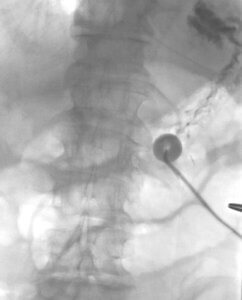

Percutaneous gastrostomy tube placement is most often performed under conscious sedation whereby two medications, typically fentanyl and versed, are administered intravenously. In certain situations, general anesthesia or a single anesthetic or anxiolytic will be administered. If not already placed prior to the procedure, a nasogastric tube is advanced into the stomach. The tube is then used to insufflate the stomach with air under fluoroscopic visualization, which serves to displace adjacent bowel and allows for easier needle puncture of the stomach. Once the stomach is inflated with air, the interventional radiologist will choose an appropriate skin entry site for the gastrostomy tube and anesthetize the region with lidocaine; the target puncture site should be within the lower body of the stomach between the greater and lesser curvatures. Two to four T-fasteners will then be advanced from the skin into the stomach, which will secure the stomach against the abdominal wall. Once secured, a small skin incision is made and a needle is advanced between the T-fasteners into the stomach under fluoroscopy. Once within the stomach, contrast is injected through the needle to confirm its position. A guidewire is then advanced through the needle and coiled within the stomach. The tract between the skin and stomach is then sequentially dilated using plastic tissue dilators or an angioplasty balloon. A gastrostomy tube is then advanced through a peel-away sheath or over an angioplasty balloon into the lumen of the stomach. Contrast is then injected into the tube to confirm appropriate positioning. Once confirmed, a retention balloon at the end of the gastrostomy tube is inflated with dilute contrast and pulled against the stomach wall. The tube is then secured to the skin and a sterile dressing is applied. The tube then remains open to an external drain bag overnight to allow for the stomach to decompress and rest. If there is no evidence of peritonitis or other complication after 12-24 hours, tube feeds can be started. The tube will need to be changed at routine intervals, often times every 3-6 months, or more frequently if required.

This fluoroscopic image shows a percutaneously inserted gastrostomy tube appropriately positioned within the stomach. Contrast injected through the gastrostomy tube is seen outlining the gastric folds. The gastrostomy balloon has been filled with dilute contrast.